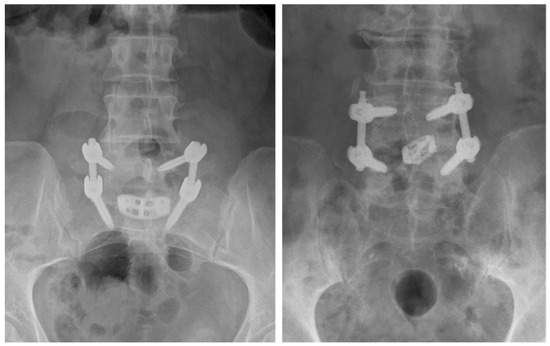

Figure 2.

Anterior-posterior lumbar radiographs of a crescent-shaped interbody device placed at the L5-S1 level (left) and a bullet-shaped interbody device placed at the L4-L5 interbody level (right).